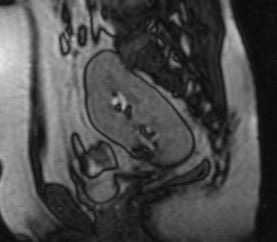

Тазовое расположение почки встречается с частотой 1 на 3000, что делает этот вариант одним из наиболее распространенных почечных эктопий. Обычно протекает бессимптомно. Хорошо определяется любым лучевым методом

МРТ почек. Сагиттальная Т1-ВИ. Тазовое расположение почки.